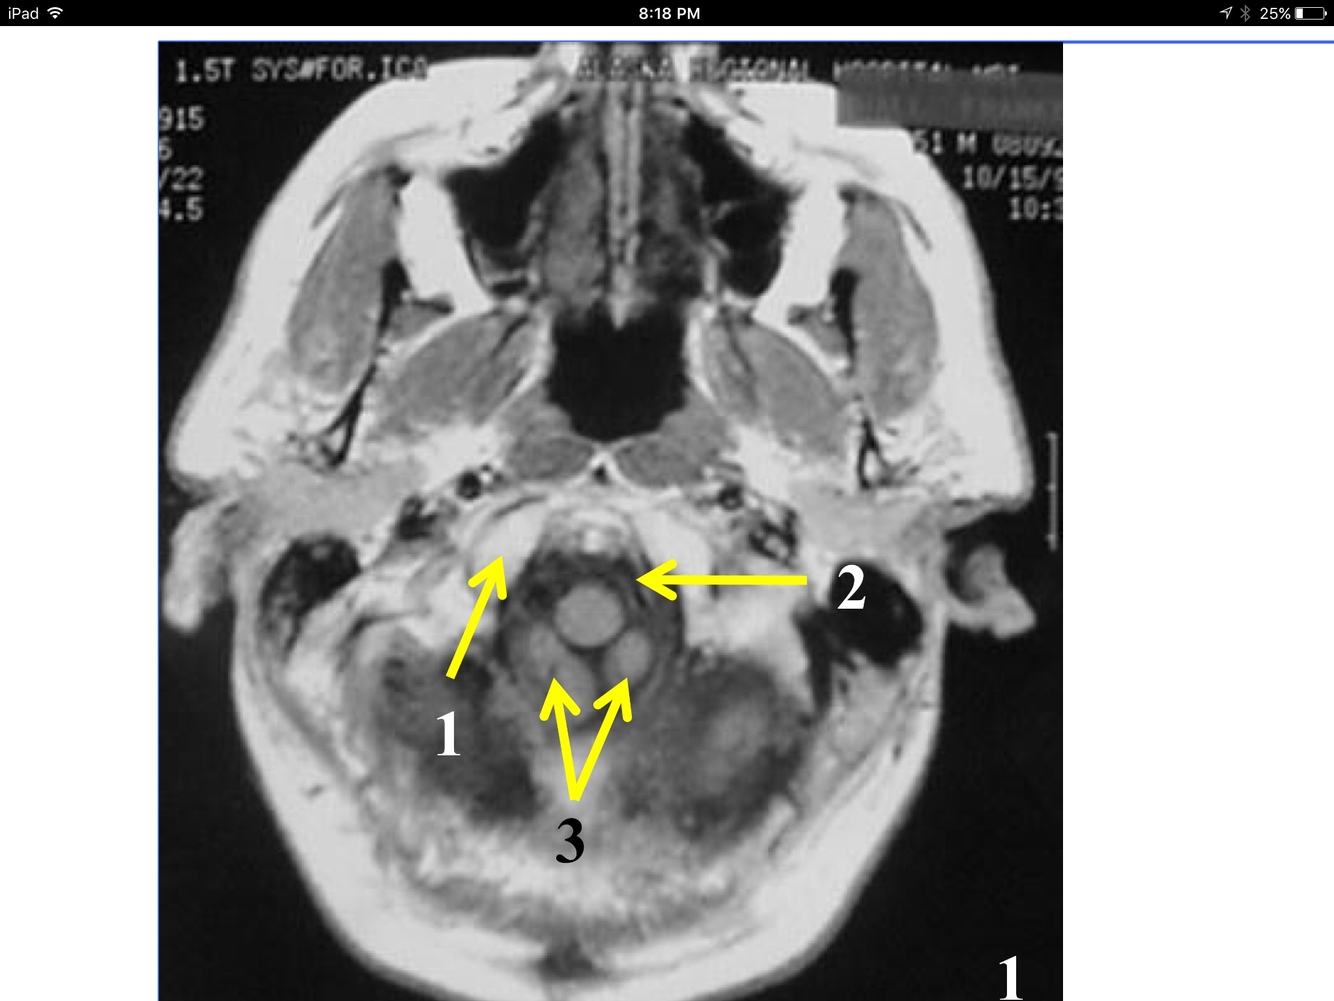

*Appears as streak as it heads fo rmidline in front of the medulla oblongata, to join the Rt vertebral and form the basilar A at the inferior and anterior to the pons.

** At the foramen magnum, entering the posterior fossa of the cranium.